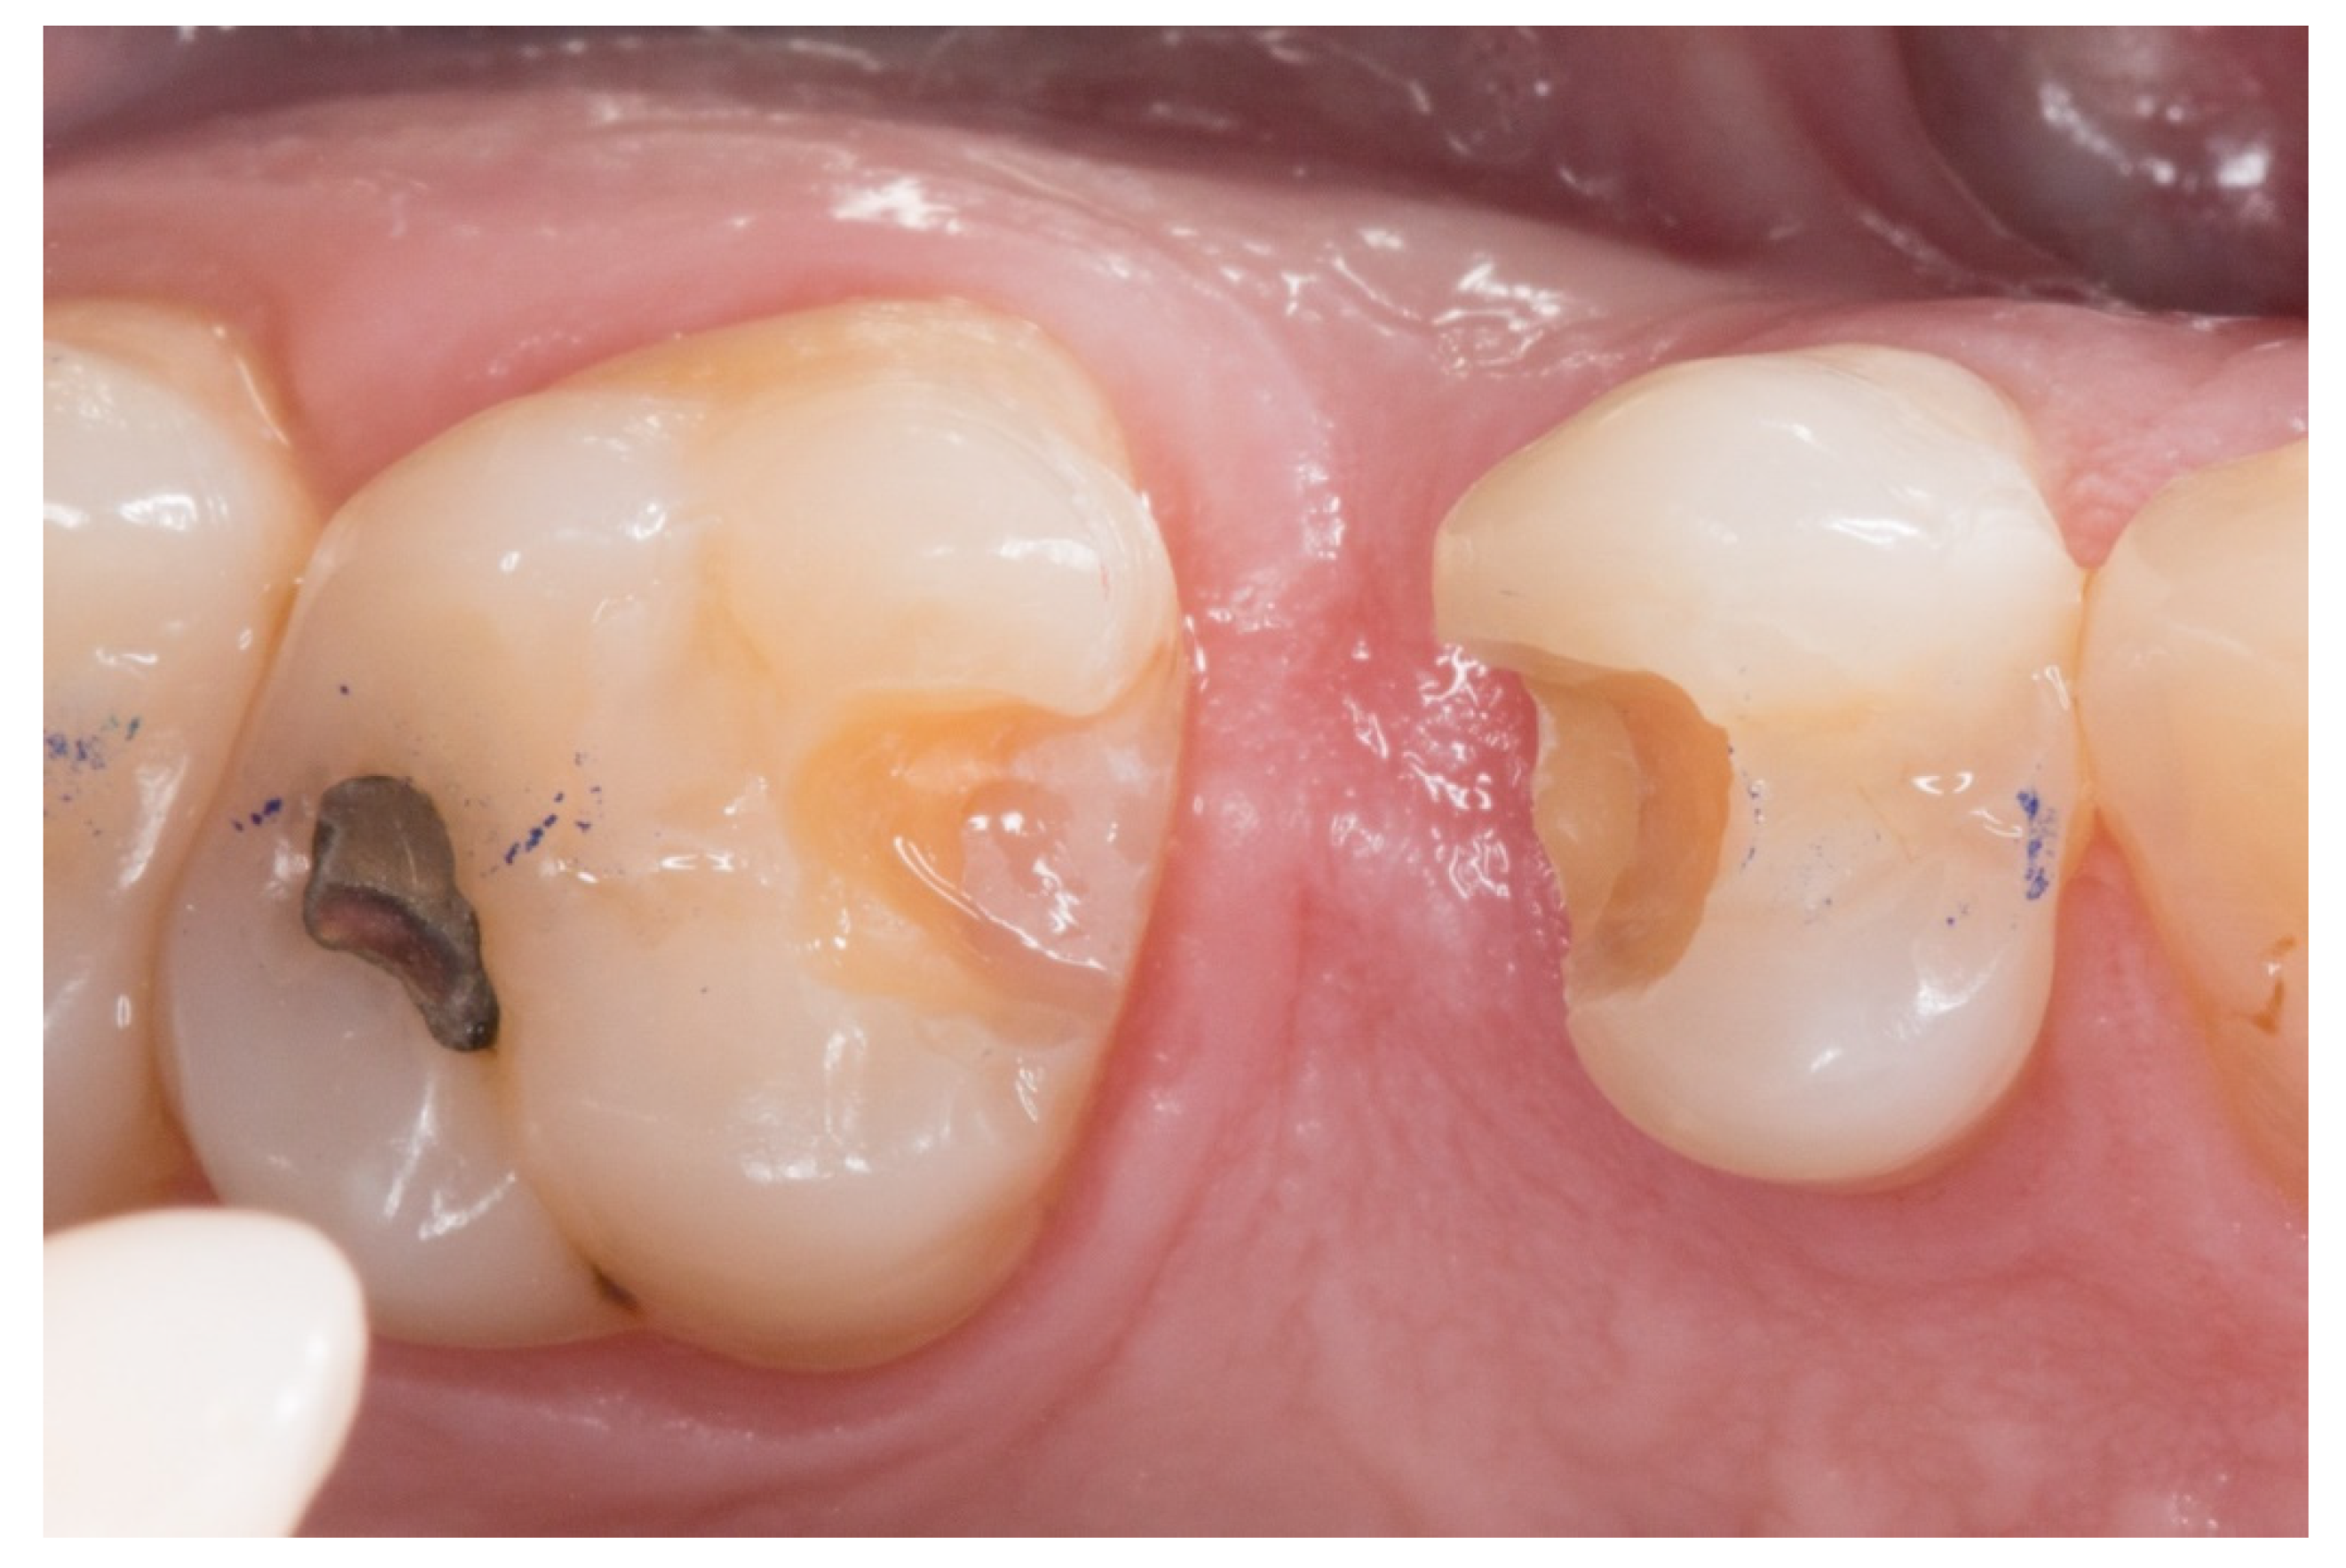

Figure 2.

The proximal faces of the adjacent teeth delimiting the edentulous space carved up to the level of the ideal point of contact (inlay cavities).

Figure 3.

The transverse structure of the future fiber-reinforced composite bridge (FRCB).

2. The proximal faces of the adjacent teeth delimiting the edentulous space were carved up to the level of the ideal point of contact (inlay cavities), to position the future horizontal structure of the fiberglass bridge (Figure 2).

3. The next step consisted of the horizontal fiberglass pin (Rebilda® Post GT, VOCO GmbH, Cuxhaven, Germany) bonding to the adjacent teeth. Firstly, when the isolation of the operative field with the rubber dam was made, the fiberglass pin was adjusted to size and silanization according to the instructions by the manufacturer. Later, the inlay cavities were etched with Ultra-etch® (Ultradent Products Inc, South Jordan, UT, USA) for 20 s, rinsed for 10 s and dried for 10 s. The etched surfaces were covered with a layer of a universal adhesive resin (Prime & Bond® NT, Dentsply Sirona Inc., York, PA, USA), thinned using a brush, and cured for 20 s with a light- polymerizing unit. A flowable resin (Tetric Evo flow®, Ivoclar Vivadent AG, Schaanwald, Liechtenstein) was used to cover the inlay cavities (inlays retainers) and the fiberglass pin to shape the transverse structure of the future bridge (Figure 3 and Figure 4).